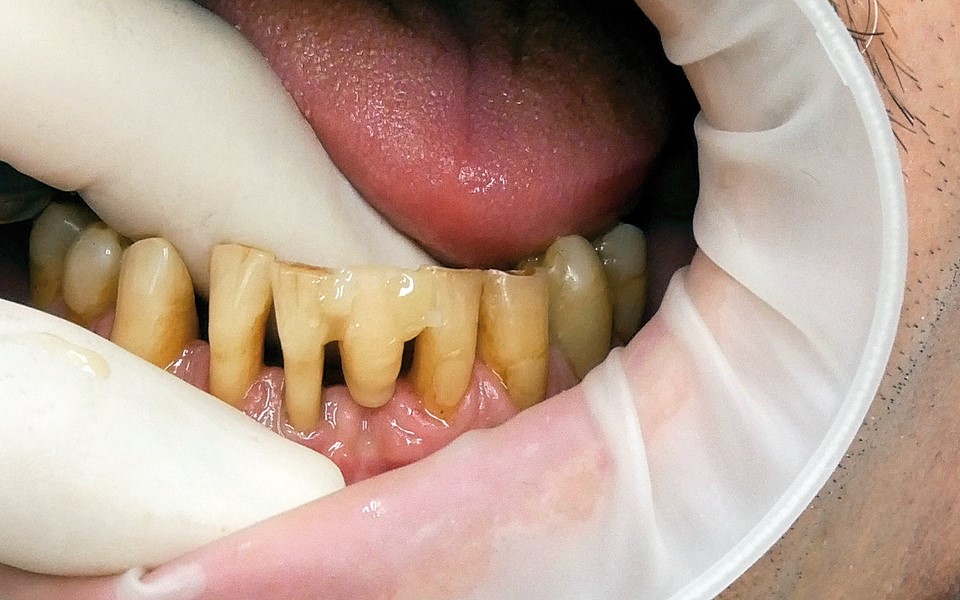

Jedną z popularniejszych metod stabilizacji zębów rozchwianych jest ich szynowanie. Metoda ta, wspierająca inne metody leczenia, jest powszechnie stosowana. Jednym z najnowocześniejszych materiałów wykorzystywanych w stomatologii do szynowania zębów jest taśma poliaramidowa. W opisanym przypadku autorzy pracy przedstawiają sposób uproszczenia całej procedury i ograniczenia ryzyka popełnienia błędu, szczególnie w sytuacji całkowitej utraty zęba. Uzyskano to dzięki zastosowaniu indeksu wykonanego z przezroczystego silikonu.

One of the more popular methods of stabilising loose teeth is to splint them. This method, aiding other methods of treatment, is generally used. One of the most modern materials used in dentistry for splinting teeth, is polyamide tape. In the case described the authors show how to simplify the whole procedure and limit the risk of making a mistake, particularly in the situation of total loss of one tooth. This was achieved thanks to the use of an index made out of transparent silicone.